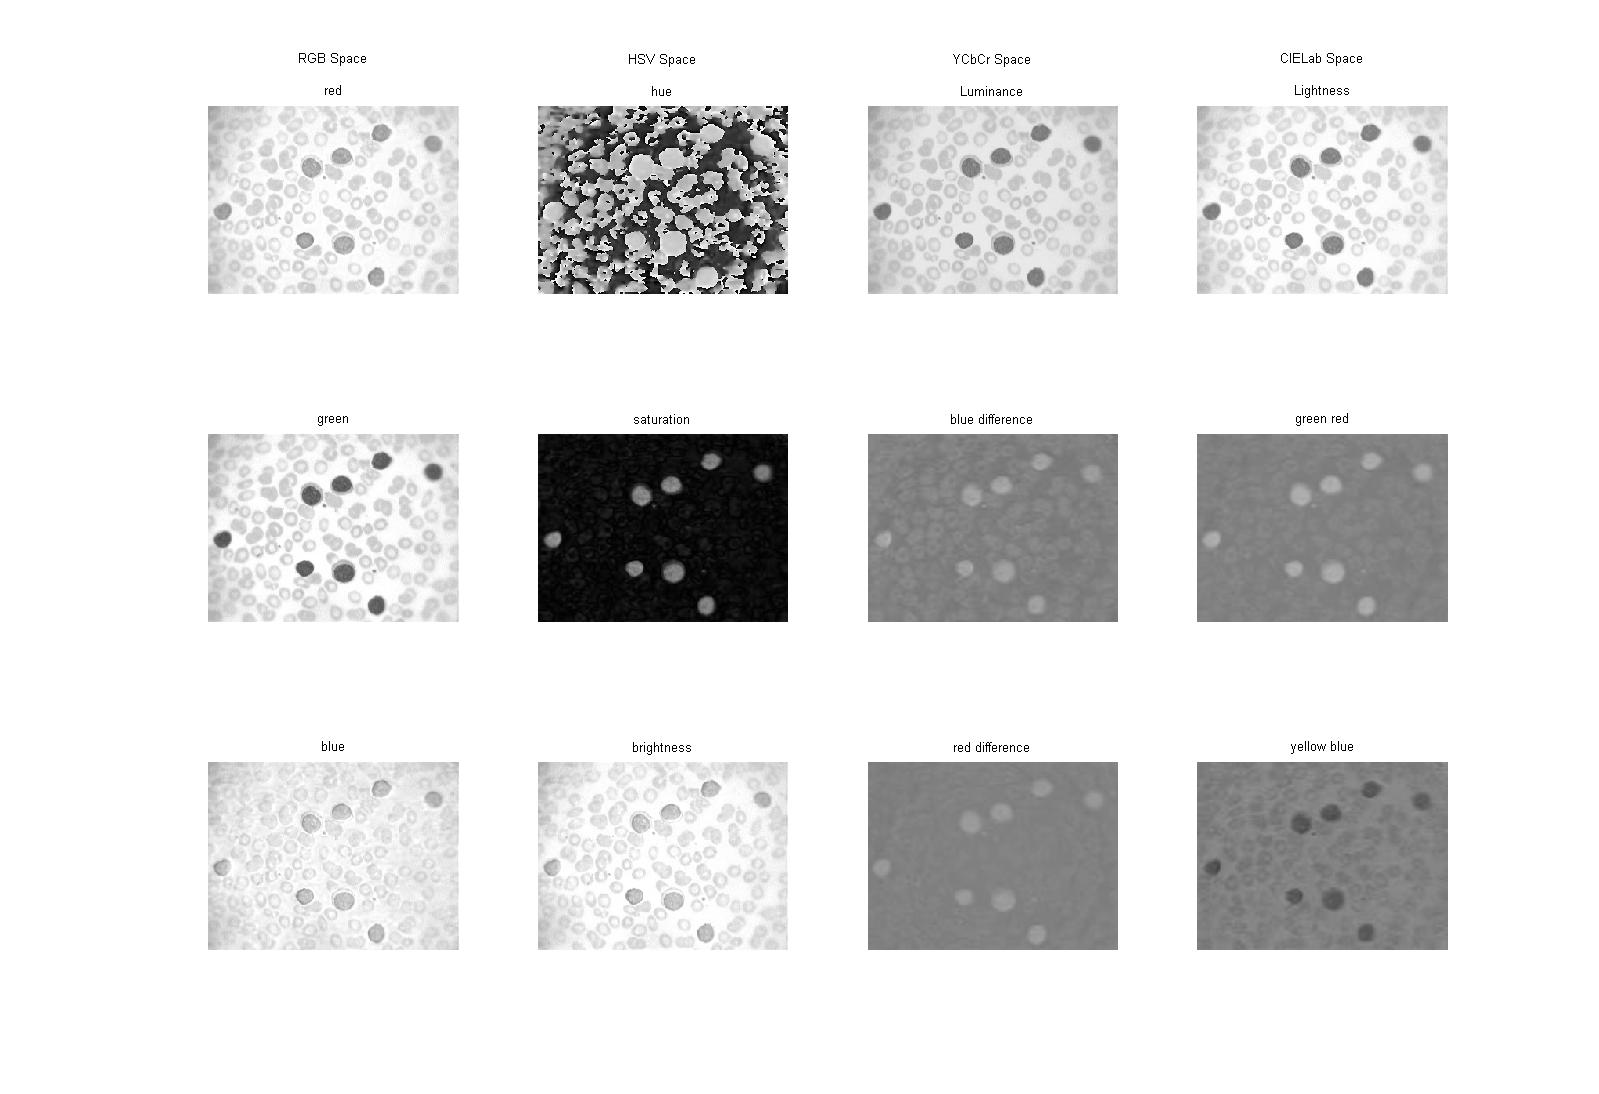

由于您没有包含语言标记,所以我想附加一些我刚刚编写的Matlab代码。它在所有4种颜色空间中显示一幅图像,这样您就可以迅速做出使用哪种颜色的明智决定。它模拟matlabs阈值机颜色空间选择窗口

function ViewColorSpaces(rgb_image)

% ViewColorSpaces(rgb_image)

% displays an RGB image in 4 different color spaces. RGB, HSV, YCbCr,CIELab

% each of the 3 channels are shown for each colorspace

% the display mimcs the New matlab color thresholder window

% http://www.mathworks.com/help/images/image-segmentation-using-the-color-thesholder-app.html

hsvim = rgb2hsv(rgb_image);

yuvim = rgb2ycbcr(rgb_image);

%cielab colorspace

cform = makecform('srgb2lab');

cieim = applycform(rgb_image,cform);

figure();

%rgb

subplot(3,4,1);imshow(rgb_image(:,:,1));title(sprintf('RGB Space\n\nred'))

subplot(3,4,5);imshow(rgb_image(:,:,2));title('green')

subplot(3,4,9);imshow(rgb_image(:,:,3));title('blue')

%hsv

subplot(3,4,2);imshow(hsvim(:,:,1));title(sprintf('HSV Space\n\nhue'))

subplot(3,4,6);imshow(hsvim(:,:,2));title('saturation')

subplot(3,4,10);imshow(hsvim(:,:,3));title('brightness')

%ycbcr / yuv

subplot(3,4,3);imshow(yuvim(:,:,1));title(sprintf('YCbCr Space\n\nLuminance'))

subplot(3,4,7);imshow(yuvim(:,:,2));title('blue difference')

subplot(3,4,11);imshow(yuvim(:,:,3));title('red difference')

%CIElab

subplot(3,4,4);imshow(cieim(:,:,1));title(sprintf('CIELab Space\n\nLightness'))

subplot(3,4,8);imshow(cieim(:,:,2));title('green red')

subplot(3,4,12);imshow(cieim(:,:,3));title('yellow blue')

end你可以这样称呼它

rgbim = imread('http://i.stack.imgur.com/gd62B.jpg');

ViewColorSpaces(rgbim)显示是这样的